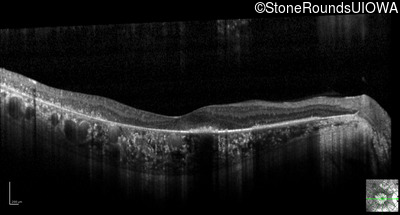

Optical Coherence Tomography - Right - 20/25

Exemplar / OCT Stack